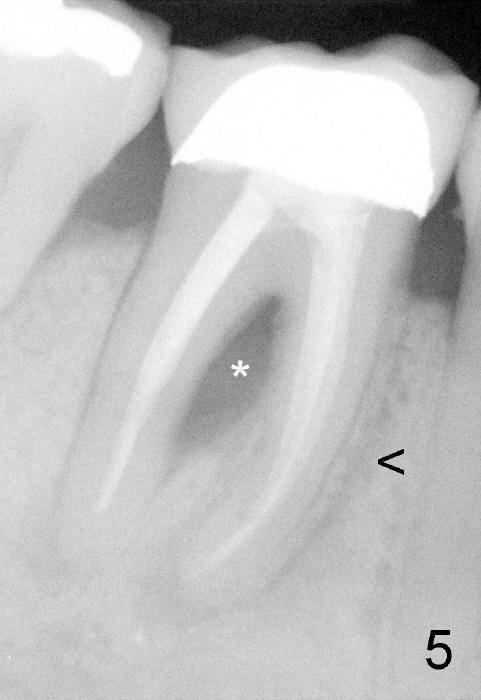

Dowman太太来自德国,收入不好,抽烟,不用牙线,结石多(图一箭头),右下第一磨牙远中龋齿(*)。她深洗还积极(图二已经没有明显结石),处理龋齿拖拖拉拉,九个月后,去龋时穿髓,暂封(图二*),她的后牙牙根特长,说明什么?下面回答。不得不做根管治疗(图三),图四是根管治疗后一年半拍摄,虽然根尖有阴影(箭头),但是病人没有任何症状。又过两年多病人主诉右下不适,根尖片显示根分叉阴影特大(图五*),近中根近中也有阴影(箭头),这时结石又出现。口内检查太容易了:右下第一磨牙颊侧有瘘道(图六双箭头),颊侧根分叉上皮附着失去(图六单箭头,也就是牙周袋深,探测出血),而舌侧根分叉牙周袋正常。总之,近中根有隐裂,接近颊侧,而远中根好像不容易出事,因为它比近中根粗。当我们为她牙齿惋惜时,老外比较爽快,说“It is not your fault. I love eating nuts. I grind my teeth at night. My night guard is too old to wear”。这段话可能说明为什么她后牙牙根长。

可能再牵强大家一次,她牙周病与根裂容易诊断有关。她再次接受深洗,由于经济问题,不肯拔牙。自从根裂诊断后,她认真搞好口腔卫生,说牙痛好多了,作为医生,这点很难理解。不过她总有一天需要拔牙,植牙。好在她已经戒烟了,为植牙奠定基础。

总之,根裂诊断容易程度取决于事先有否牙周病,断裂是否接近牙周袋。